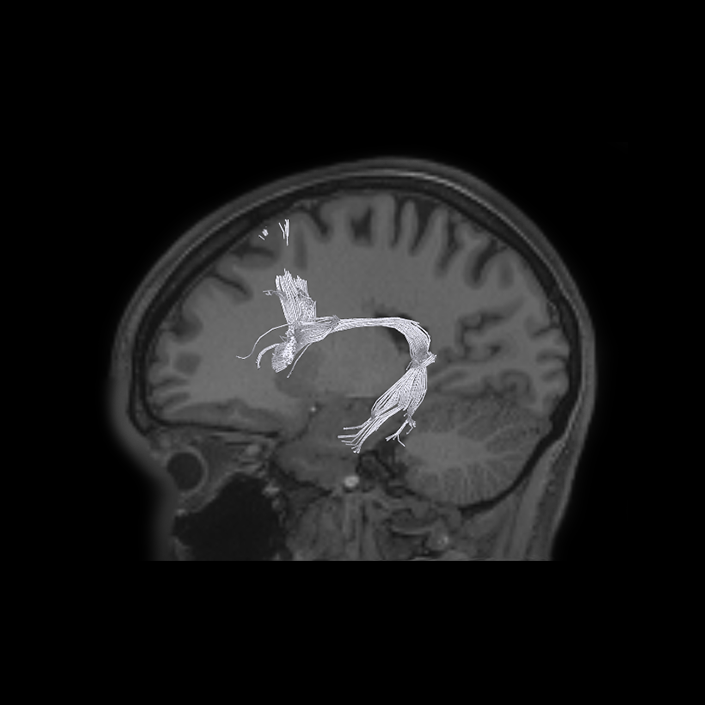

ᐅ SummaryArea IFJa (inferior frontal junction, anterior): part of the lateral frontal lobe. Areas in the midventrolateral prefrontal cortex interact with posterior areas of the brain to retrieve specific auditory memories. The inferior frontal junction, in particular, serves as an important crossroads between bottom-up and top-down processing in the lateral prefrontal cortex. ᐅ Where is it?Area IFJA is located in the posterior portion of the inferior frontal sulcus. It comprises part of the inferior bank of the MFG in its upper portions. It is roughly superior to the pars opercularis portion of the inferior frontal gyrus. ᐅ What are its borders?Area IFJa borders area IFSp anteriorly and IFJp posteriorly. Its inferior border is area 44 and its superior border is area 8C. ᐅ What are its functional connections?Area IFJa demonstrates functional connectivity to areas 44, IFSa, IFSp, IFJp, and p9-46v in the dorsolateral frontal lobe, area SCEF in the medial frontal lobe, areas FEF, 55b PEF and 6r in the premotor areas, area FOP5 and PSL in the insular opercular regions, areas PH, PHT, and TE2p in the temporal lobe, areas MIP, TPOJ1, and LIPd in the inferior parietal lobe, and no areas in the medial parietal lobe. ᐅ What are its white matter connections?Area IFJa is structurally connected with the arcuate/SLF and surrounding parcellations. Connections with the arcuate/SLF project posteriorly and wrap around the Sylvian fissure to the middle and inferior temporal gyrus to end at TE1a, TE1m, and TE2a. There are also fibers that project superiorly form IFJa to end at SFL. These fibers are likely portions of the frontal aslant tract which has the majority of its inferior terminations at 44, a neighbor of IFJa. Local short association bundles connect to 8c, IFJa, IFSp, 44 and 8A. ᐅ What is known about its function?Areas in the midventrolateral PFC interact with posterior areas of the brain to retrieve specific auditory memories. The IFJ, in particular, serves as an important crossroads between bottom-up and top-down processing in the lateral prefrontal cortex. |

A: lateral-medial

B: anterior-posterior

C: superior-inferior

DTI image |